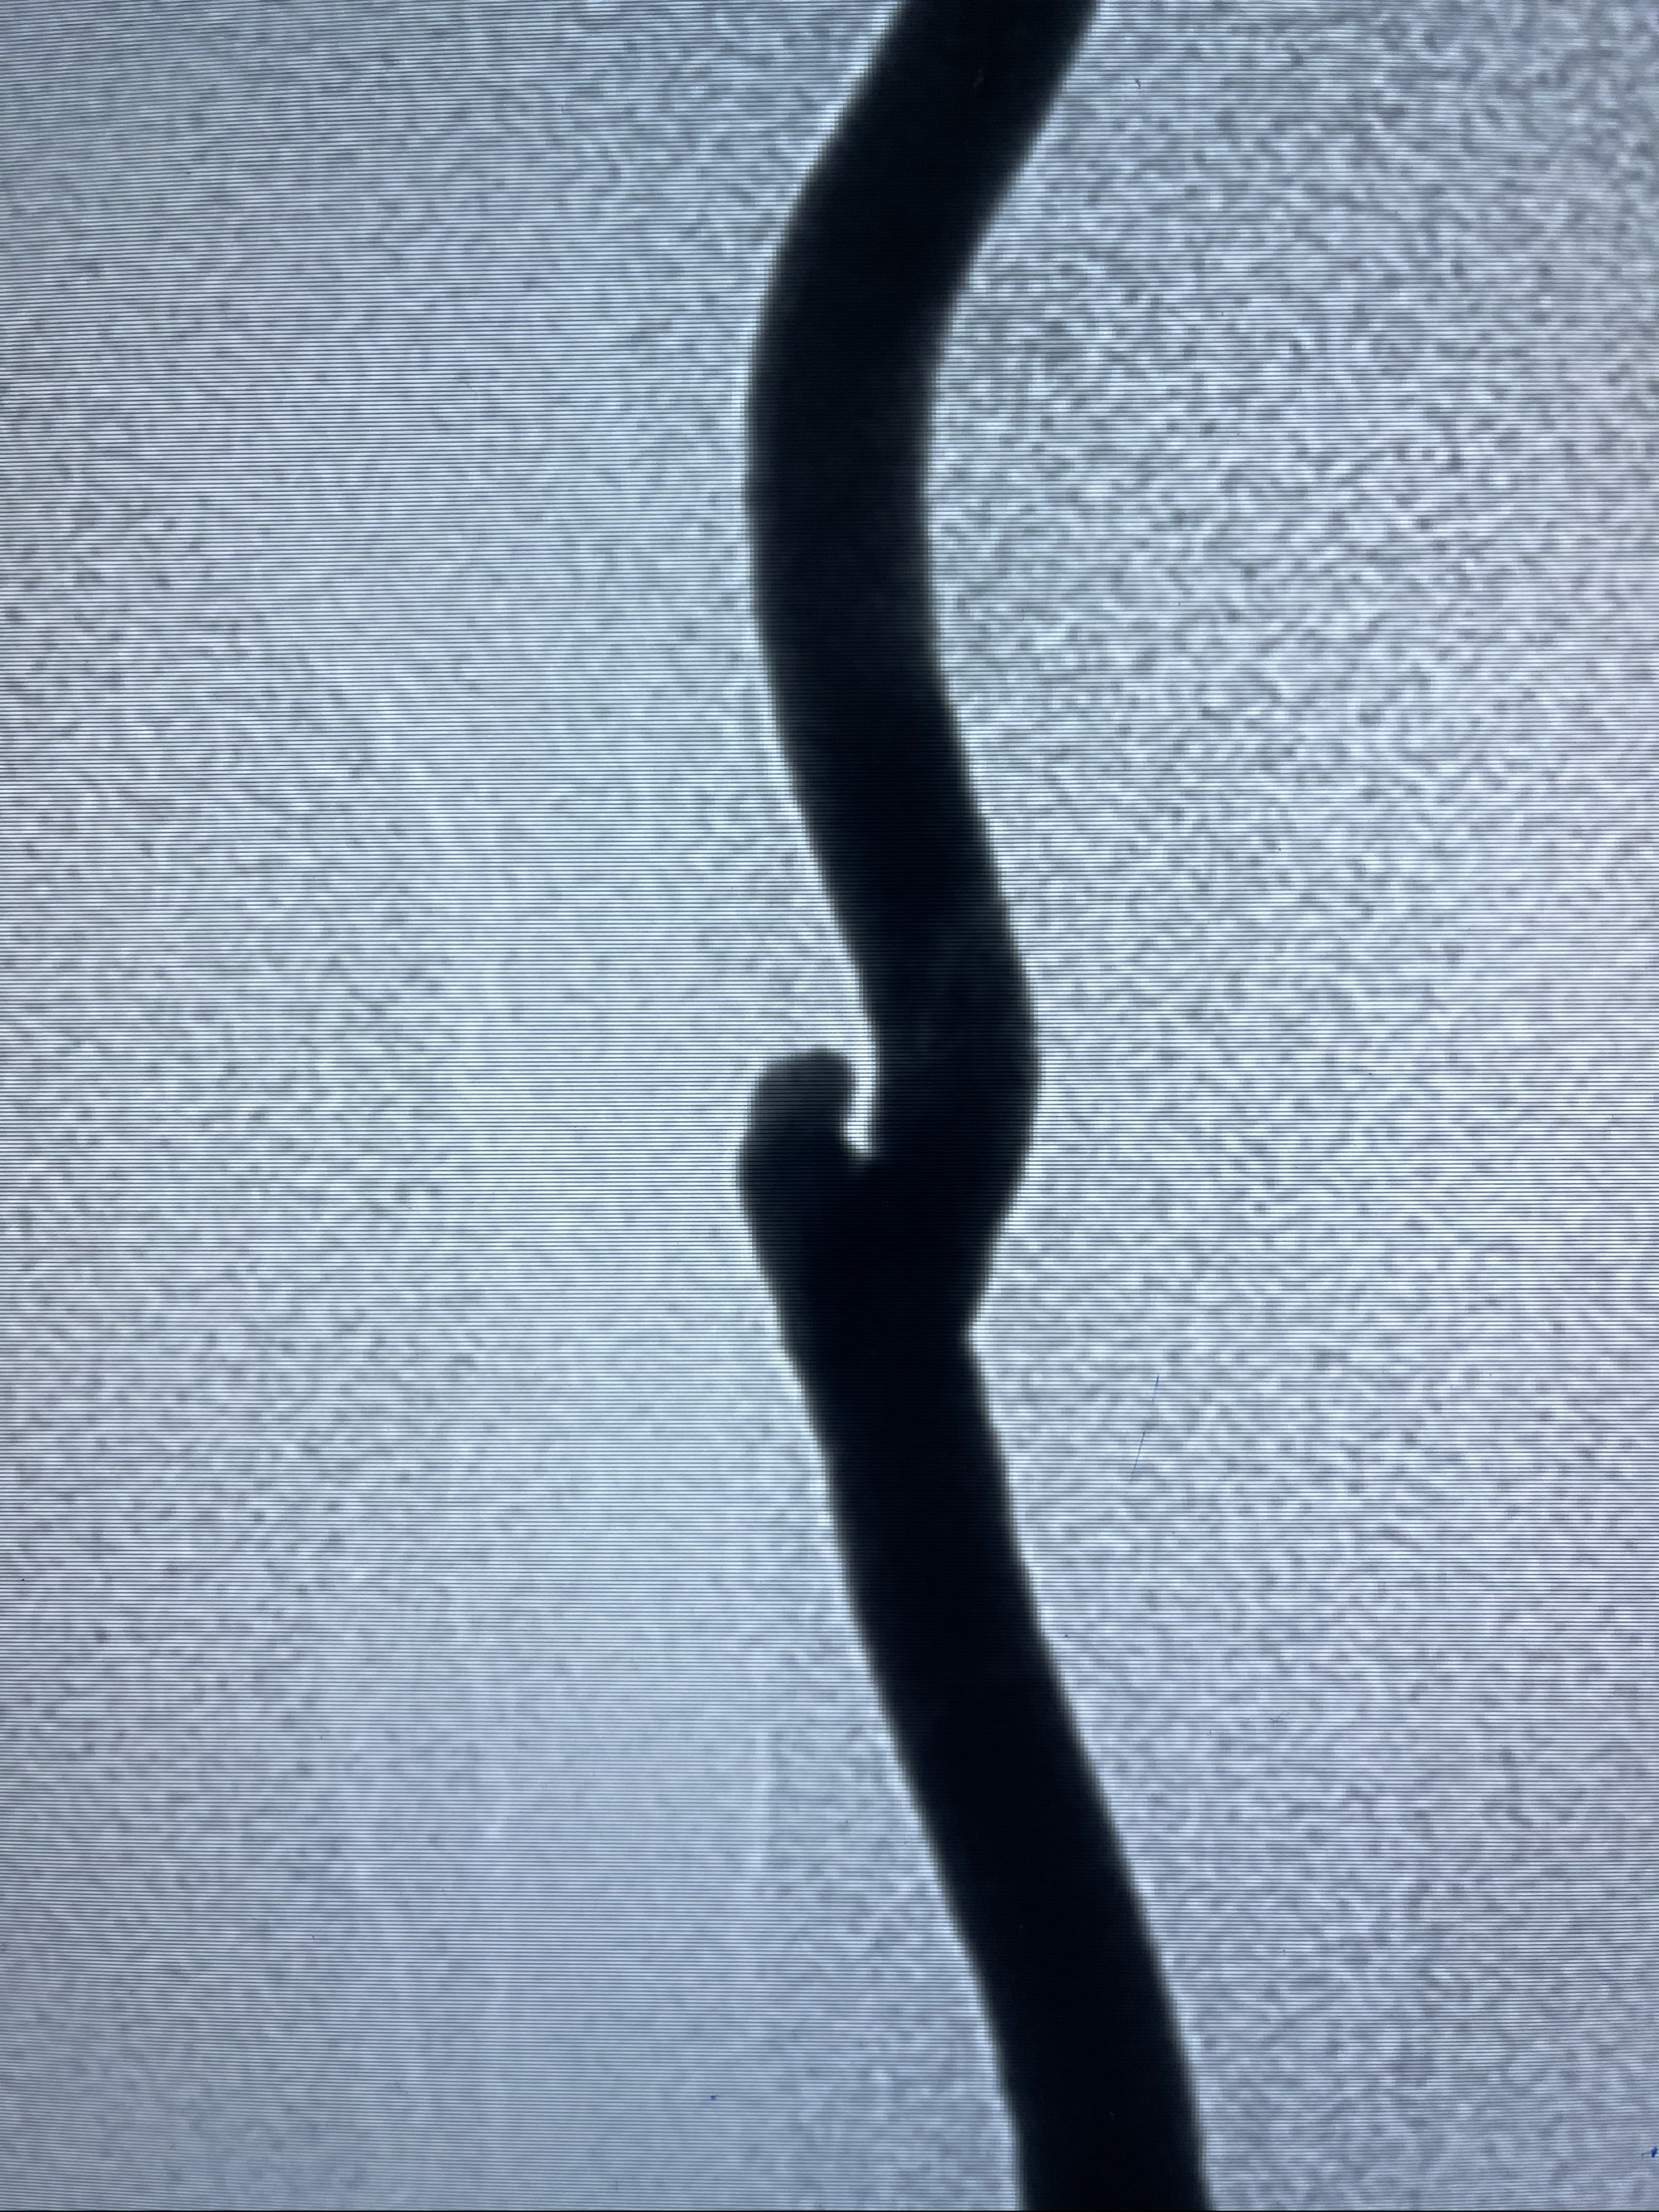

工作角度造影

8mm-40cm微弹簧圈成篮

即刻造影